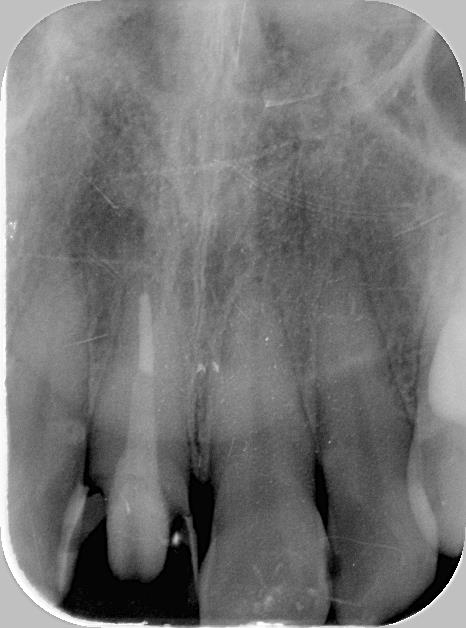

根管治療後の土台コア装着後のレントゲン写真